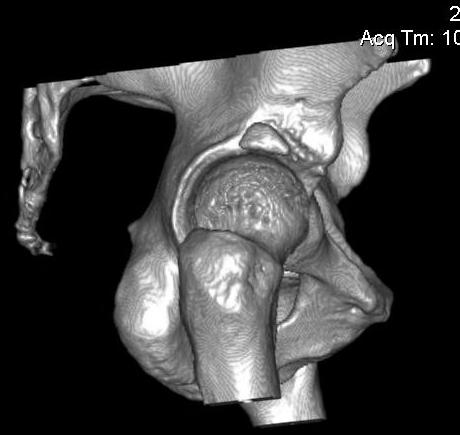

Добавляю снимков для "информационной поддержки принятия решения" (ну, нравится мне это выражение )). Поступило предложение выполнить артроскопию для оценки сохранности хряща. Насколько это необходимо?